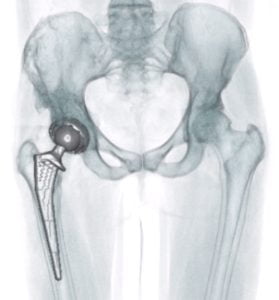

A Prótese da Anca ou Artroplastia da Anca é a substituição da articulação coxofemoral por um implante ortopédico.

Esta cirurgia é uma solução quando o desgaste da cartilagem é relevante, acompanhado de dor significativa e perda de mobilidade. A indicação mais frequente para a cirurgia de substituição é a artrose da anca (Coxartrose).

É um procedimento cirúrgico seguro que ajuda a aliviar a dor, a aumentar a amplitude de movimentos e permite o regresso à maioria das atividades diárias.